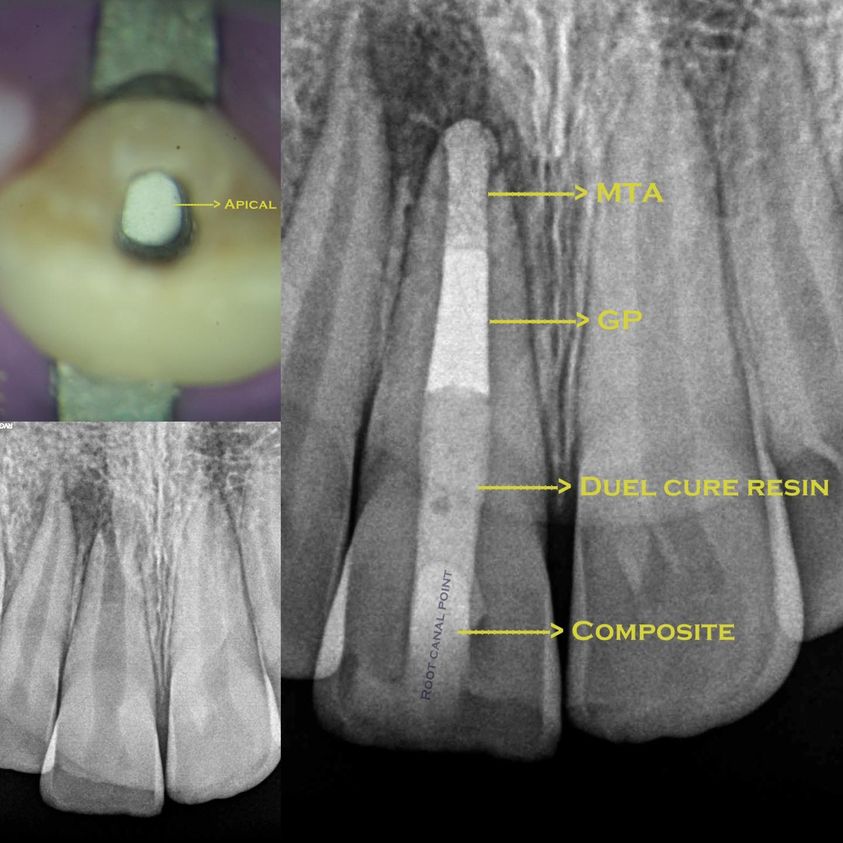

Apexification chez l’enfant

L’objectif de cette thérapeutique est de retirer le tissu pulpaire (« nerf ») nécrosé et d’induire au niveau apical, via un biomatériau …